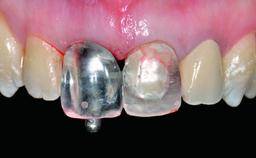

Replacement of an Upper Right Central Incisor with Root Resorption: Ridge Preservation, Early Placement of an RC Bone Level Implant

A 49-year-old female patient was referred for implant therapy to replace the upper right central incisor (tooth 11). The tooth had been assessed by an endodontist who diagnosed a vertical fracture of the root. The tooth had a hopeless prognosis and needed to be extracted. The patient was healthy and was not taking any medications. She was allergic to penicillin. The patient had high esthetic demands but her expectations were realistic. The extraoral examination revealed no facial asymmetries. The right temporomandibular joint demonstrated an opening click but was otherwise asymptomatic. The lip line was high with a significant gingival display.